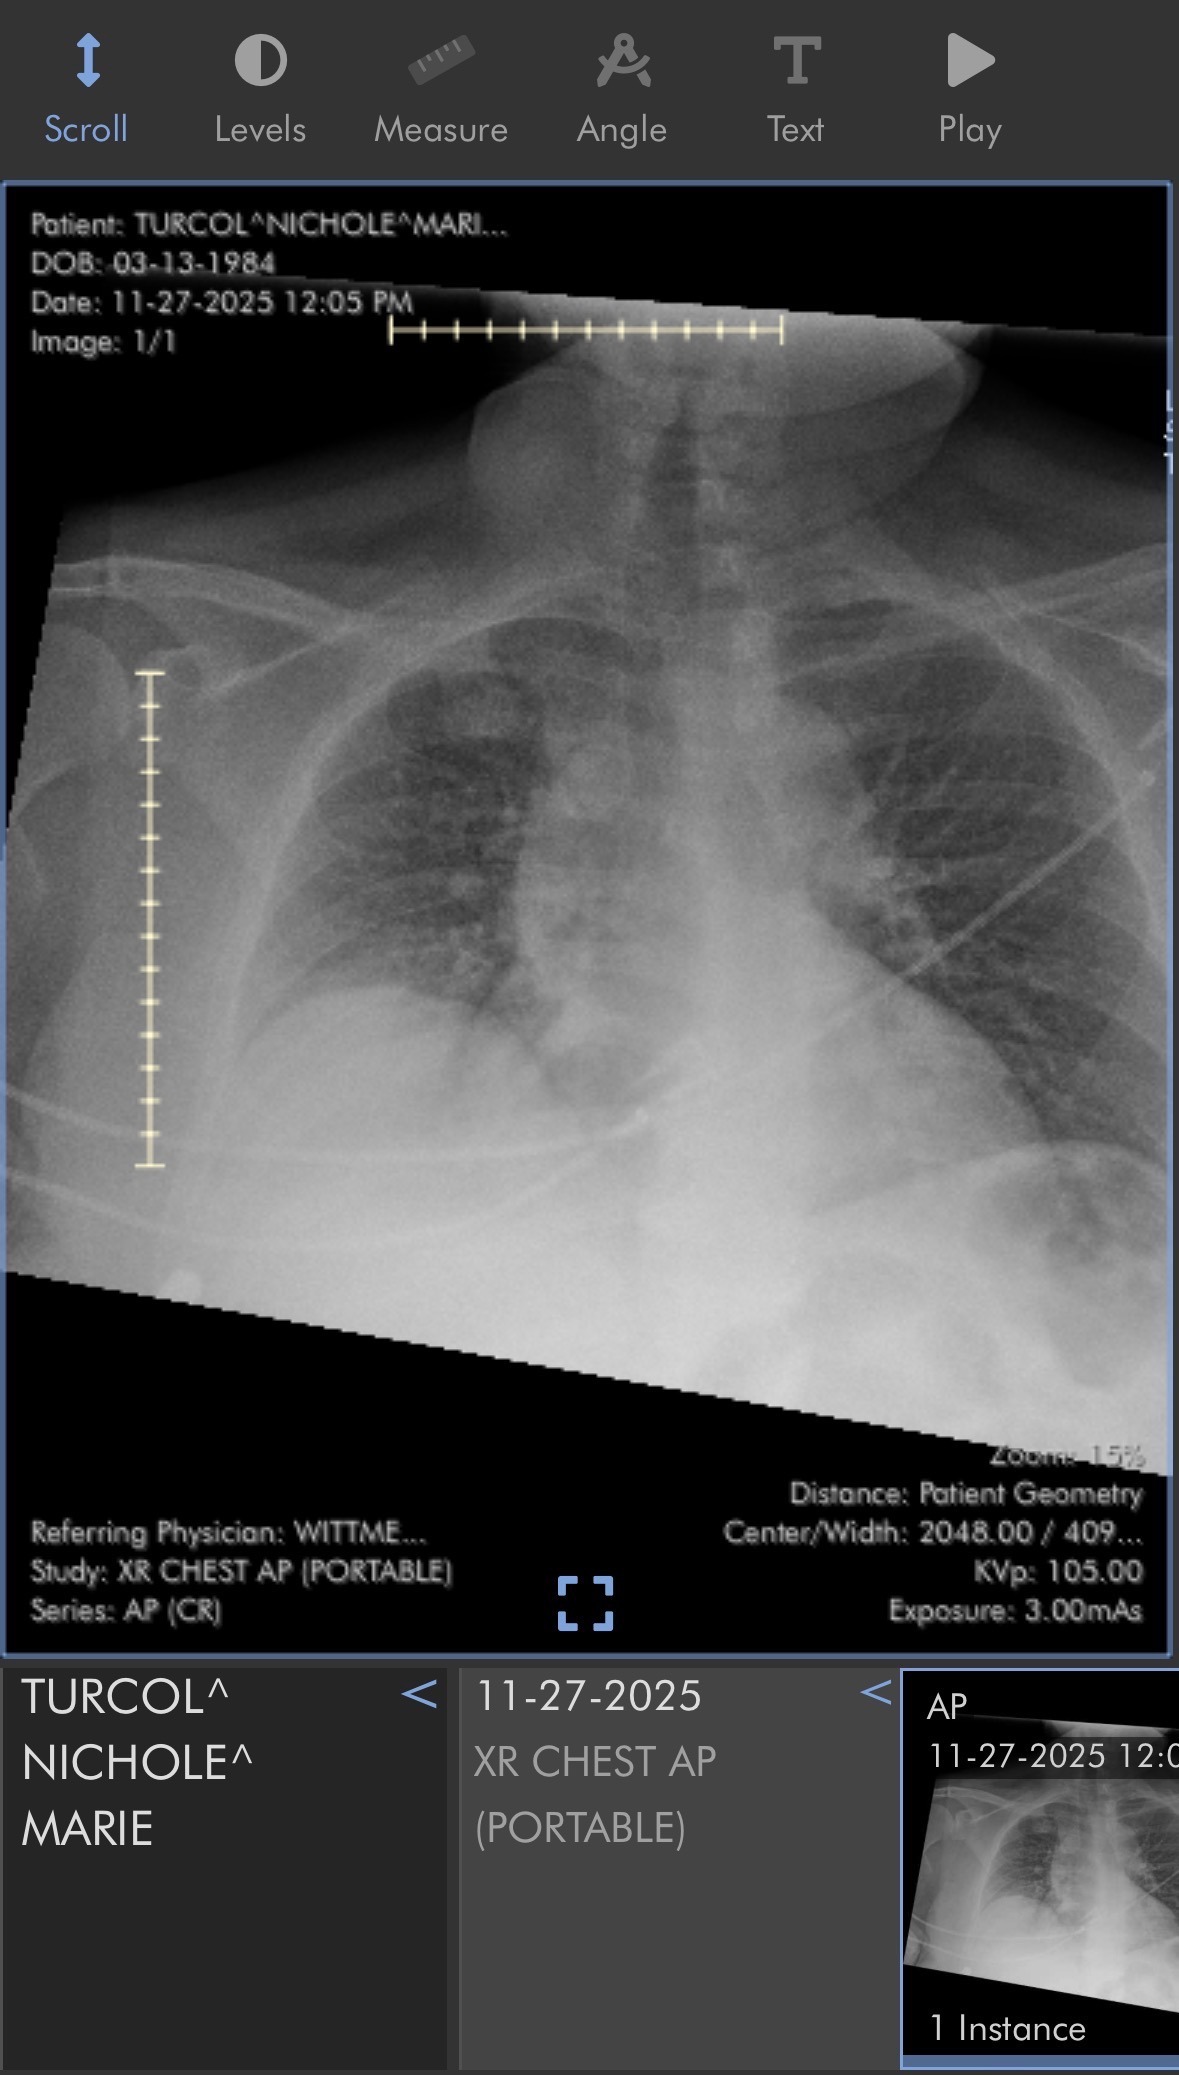

Nicki is currently suffering from a GSW entry and exit of the right hand / wrist resulting in broken center finger and nerve disruption. GSW entry to the right side of her upper chest , breaking the right side of her center ribs, leaving the bullet encased permanently. Despite the trauma, she is determined to heal, rebuild, and create a safe, stable future for herself and her young son. This is not going to be easy.